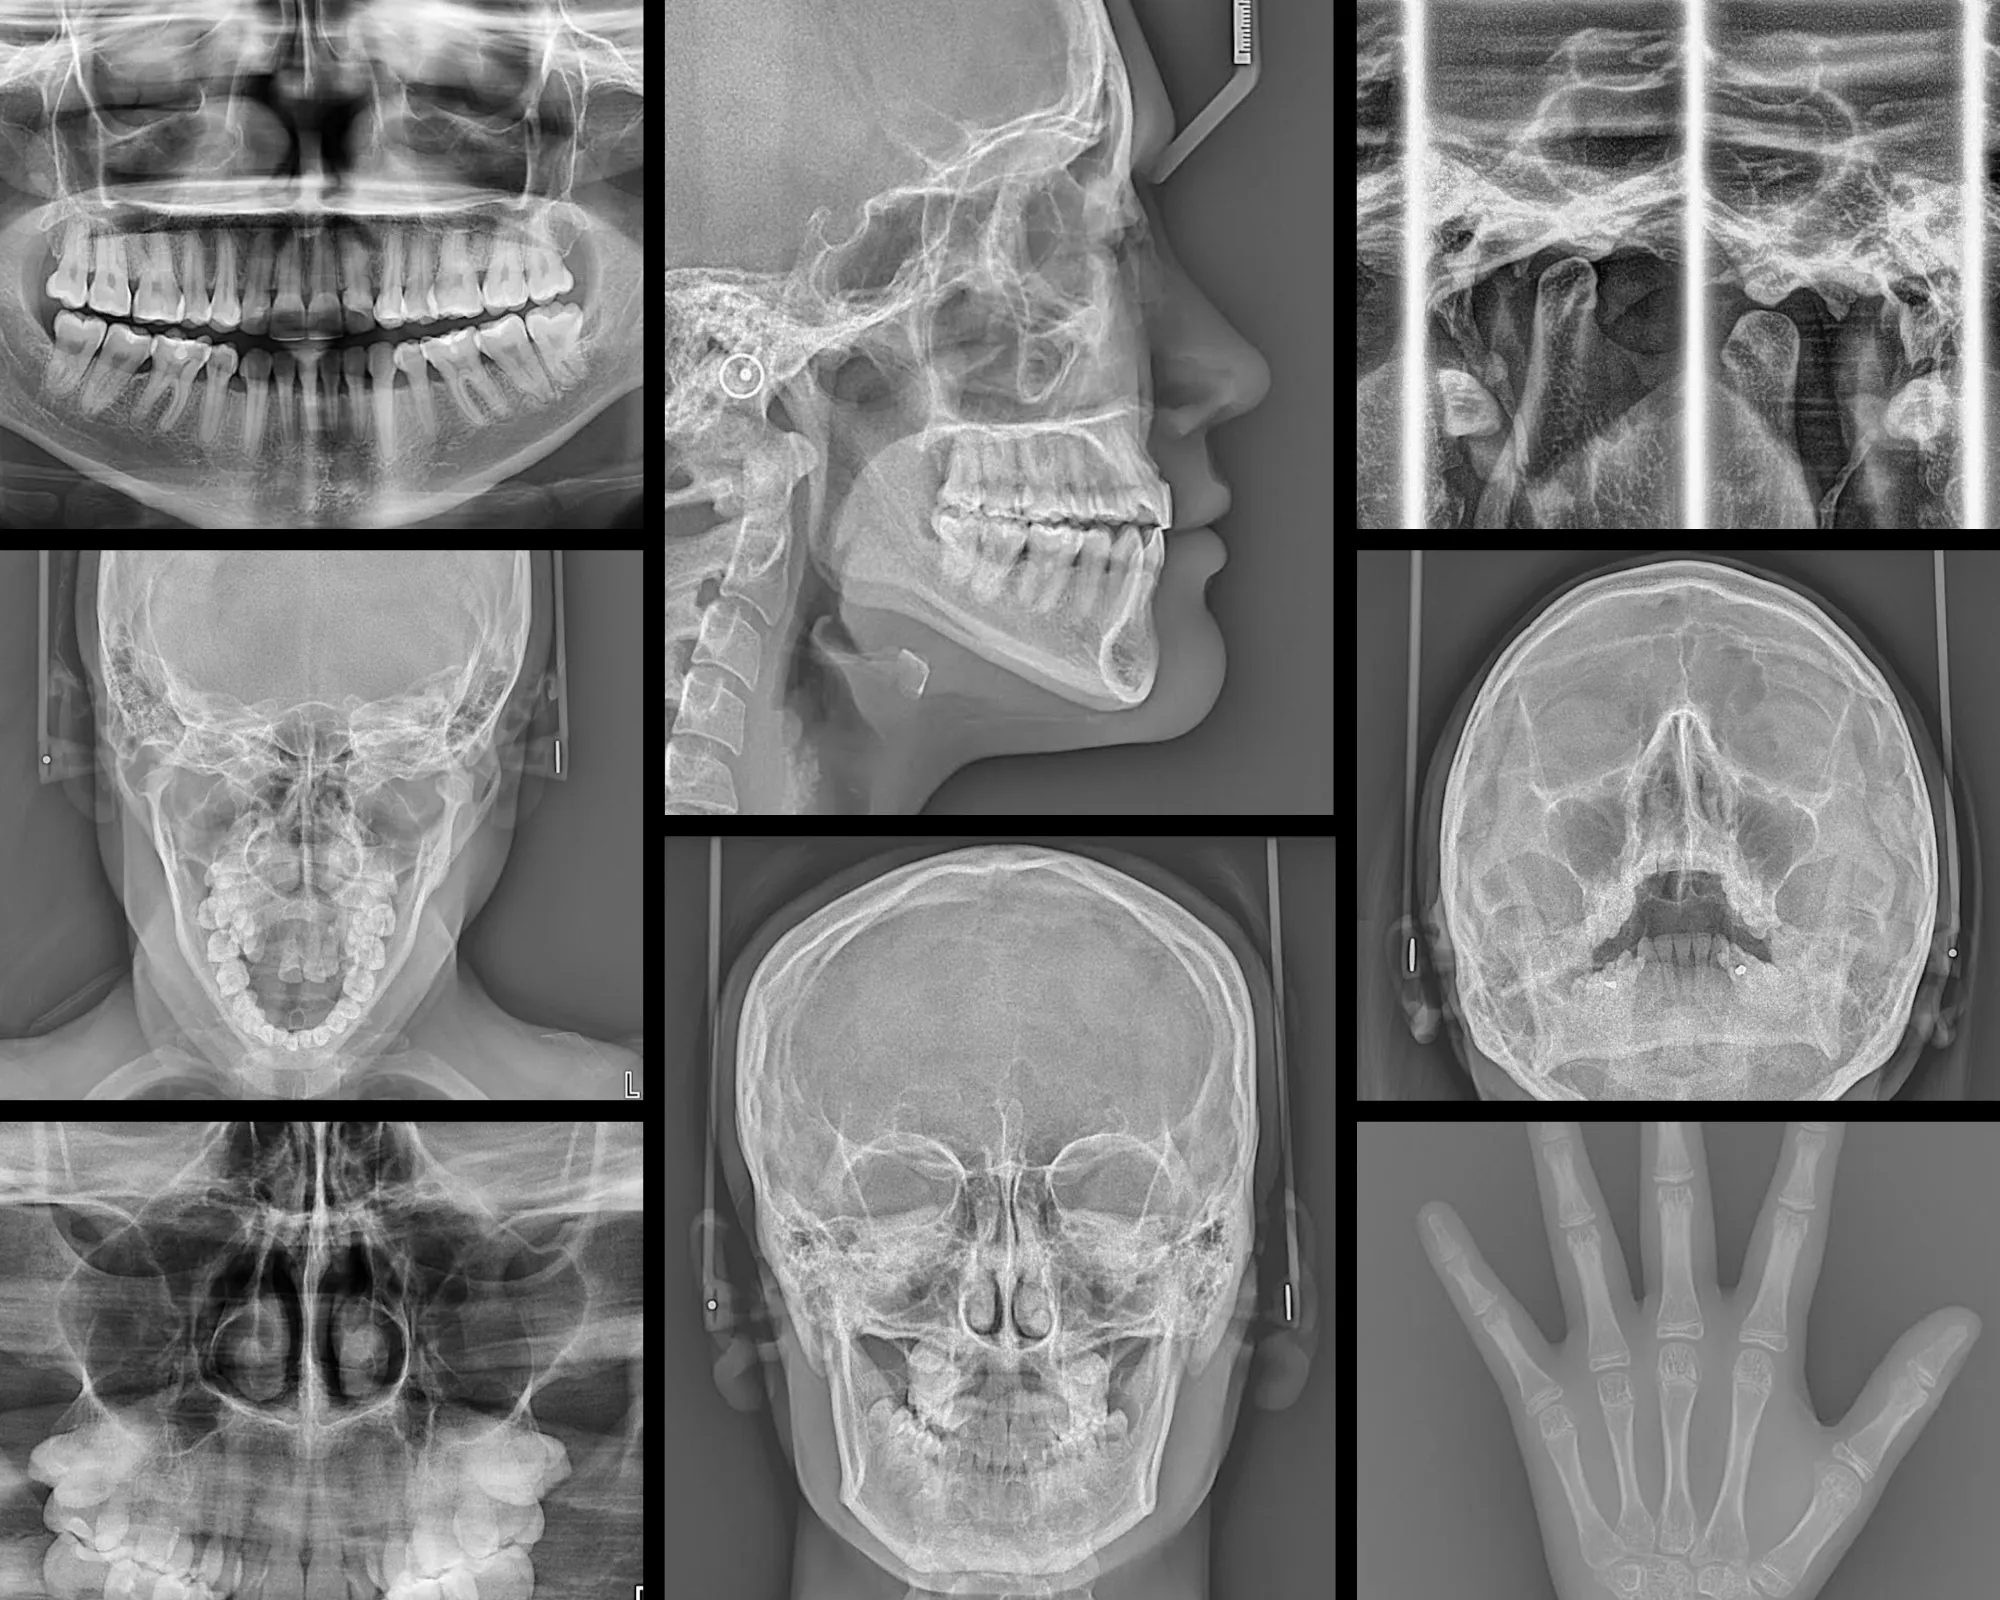

RADIOGRAFÍAS

Contamos con las siguientes radiografías:

• Radiografía Panorámica.

• Radiografía Cefalométrica Lateral.

• Radiografía ATM: Boca Cerrada / Boca Abierta.

• Radiografía Senos Paranasales.

• Radiografía Senos Maxilares (Waters).

• Radiografía Carpal.

• Radiografía Inversa de Towne.

• Radiografía Postero - Anterior (frontal).

TOMOGRAFÍAS

Contamos con las siguientes tomografías:

• Tomografía de Maxilar Superior.

• Tomografía de Maxilar Inferior.

• Tomografía de ambos Maxilares.

• Tomografía de ATM: Boca Cerrada / Boca Abierta.

• Tomografía Maxilofacial.

• Tomografía de Pieza Dentaria.

Radiopacas intraósea

Presencia de 3 imágenes radiopacas intraósea de densidad dentaria compatible con odontomas compuestos proyectados.

• 2 en zona de pieza 11

• 1 en zona de pieza 43

Odontoma Compuesto

Imagen hiperdensa localizada en el maxilar superior izquierdo, ocasionando el desplazamiento de la tabla ósea bucal y desplazamiento palatino de la pieza 2.4.

DEFECTO DE STAFNE